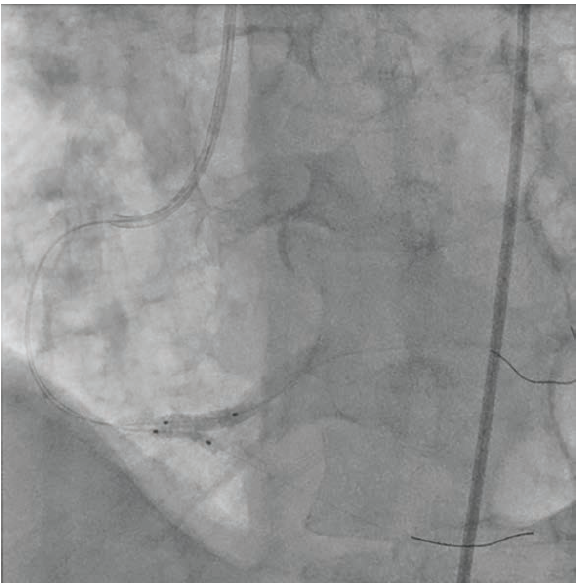

A 53-year-old male with chest pain and shortness of breath was diagnosed with complex bifurcation disease. Coronary angiography revealed a 99% bifurcation stenosis of the distal right coronary artery (RCA), with significant disease extending into the right posterior descending artery (RPDA) and right posterolateral artery (RPL) (Figure 1). Intravascular ultrasound (IVUS) revealed a 4.0 mm distal RCA and RPL, and a 3.0 mm proximal RPDA. Using the double kissing crush (DK crush) technique, .014-inch coronary wires were placed in both vessels. A 3.0 mm x 15 mm drug- eluting stent was placed in the RPDA, with 1-2 mm protrusion into the distal RCA.